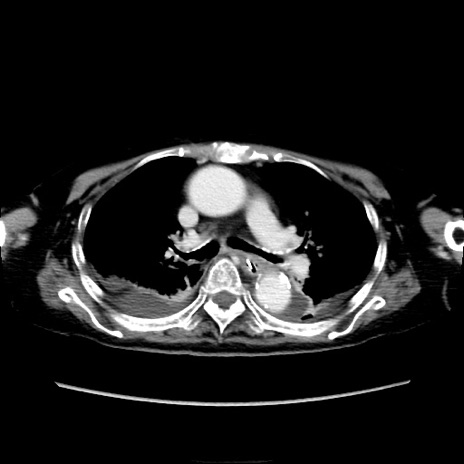

症例40(横断像)

【症例】90歳代女性

【主訴】腹痛・嘔吐

【現病歴】 食欲低下、嘔吐があり昨日他院受診。肺炎と診断され入院となる。入院後より腹部全体に圧痛あり。胃管留置され経過みていたが、症状持続するため、

当院転院となる。

【既往歴】胸椎圧迫骨折、胆石症

【身体所見】腹部:中央に激痛あり、圧痛あり、反跳痛不明

【データ】WBC 17100、CRP 18.82

横断像